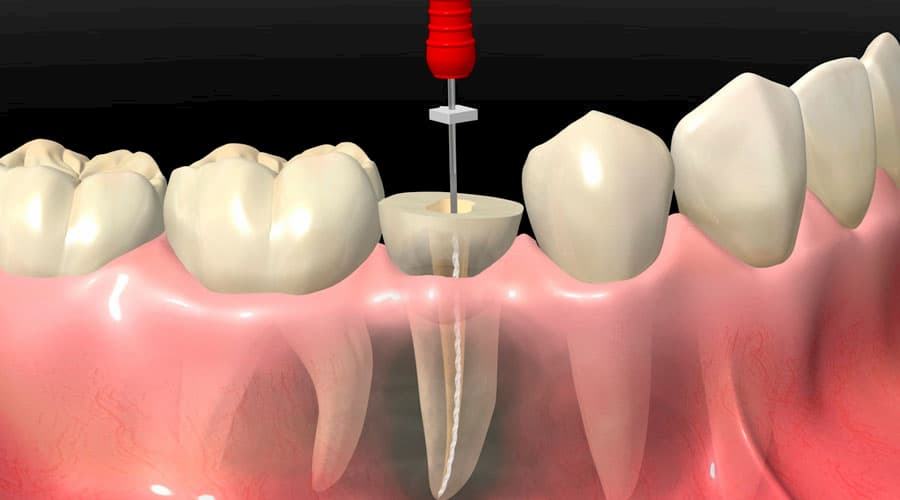

La endodoncia, conocida también como tratamiento de conducto, es un procedimiento que elimina el nervio dañado o infectado de un diente, limpiando y sellando su interior.